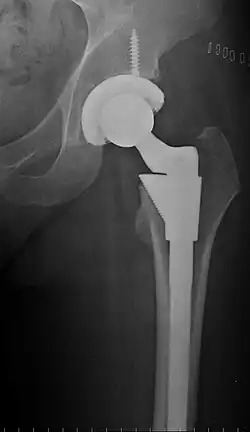

Configuration

Post-operative projectional radiography is routinely performed to ensure proper configuration of hip prostheses.

The direction of the acetabular cup influences the range of motion of the leg, and also affects the risk of dislocation.[16] For this purpose, the acetabular inclination and the acetabular anteversion are measurements of cup angulation in the coronal plane and the sagittal plane, respectively.